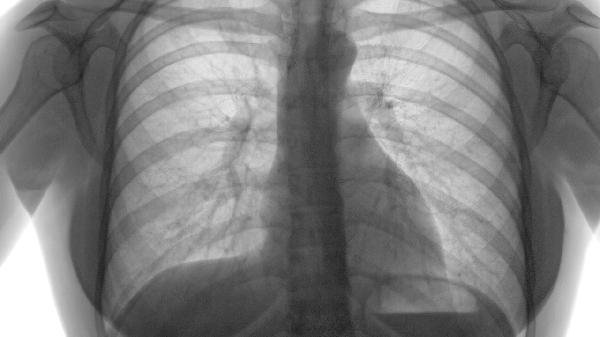

重度肺气肿患者应保持低盐高蛋白饮食,每日分5-6次少量进食避免膈肌上抬影响呼吸;进行缩唇呼吸和腹式呼吸训练可改善通气效率;冬季注意保暖防感冒,居家氧疗需维持血氧饱和度在90%以上;选择八段锦、太极拳等温和运动,运动时携带便携式氧气;定期复查肺功能与胸部CT,当出现意识模糊、紫绀等呼吸衰竭表现时需立即急诊救治。